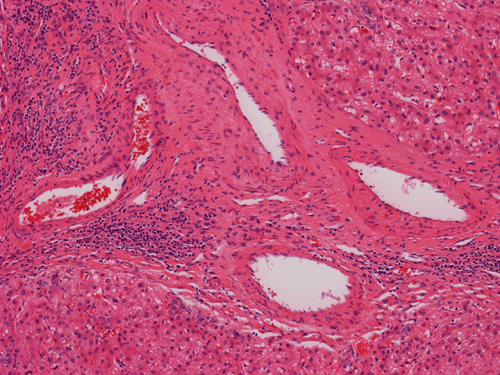

Histologically, the grossly notable nodules correspond to islands of cells separated by dense fibrous tissue  (Panel B). On medium magnification, the islands of cells have smooth, pushing margins (Panel C). The cells are quite similar to normal hepatocytes except that these islands do not have the general architecture of normal liver (Panel D). The liver plate varies from one to three cell thick is well demonstrated by reticulin stain (Panel I). In some areas there are some entrapped ductular structure consistent with bile ductules (Panel E and F) and they are well demonstrated by immunohistochemistry for cytokeratin 7 (Panel J and K). Most of these ductules are found around the fibrous scar or septa or at the edge of the nodules. Many abnormally large blood vessels are also noted and many of them are seen in the fibrous central scar (Panel G and H).

The histopathologic triad of FNH is bland hepatocytes without abnormal architecture, preserved reticulin network, the presence of bile ductules, central scar with fine fibrous septa radiating out, and the presence of large and abnormal blood vessels surrounded by a zone of connective tissue.

The central scar is composed of dense collagenous fibrous tissue with a variable number of tortuous thick-walled arteries. Fibromascular hyperplasia and myxoid degeneration are often found in these vessels.The areas away from the scaring portion and the fibrotic septa would look like normal liver at scanning magnifications. The key feature at low magnification is that no normal portal triads, no central vein or portal arteries are present. Instead, bile ductules are usually evident and often associated with chronic inflammatory cell infiltration.

Histologically, the cells in FNH are  almost identical to the normal hepatocytes surrounding hepatocytes. The reticulin network is preserved and the liver plate varies from one to three cells thick. The cells in FNA  may possess increased cytoplasmic glycogen content, focal steatosis, bile stasis, lipofuscin, iron pigment, copper deposits and Mallory bodies 4.   The central scar is composed of dense collagenous fibrous tissue with a variable number of tortuous thick-walled arteries. Fibromascular hyperplasia and myxoid degeneration are often found in these vessels.